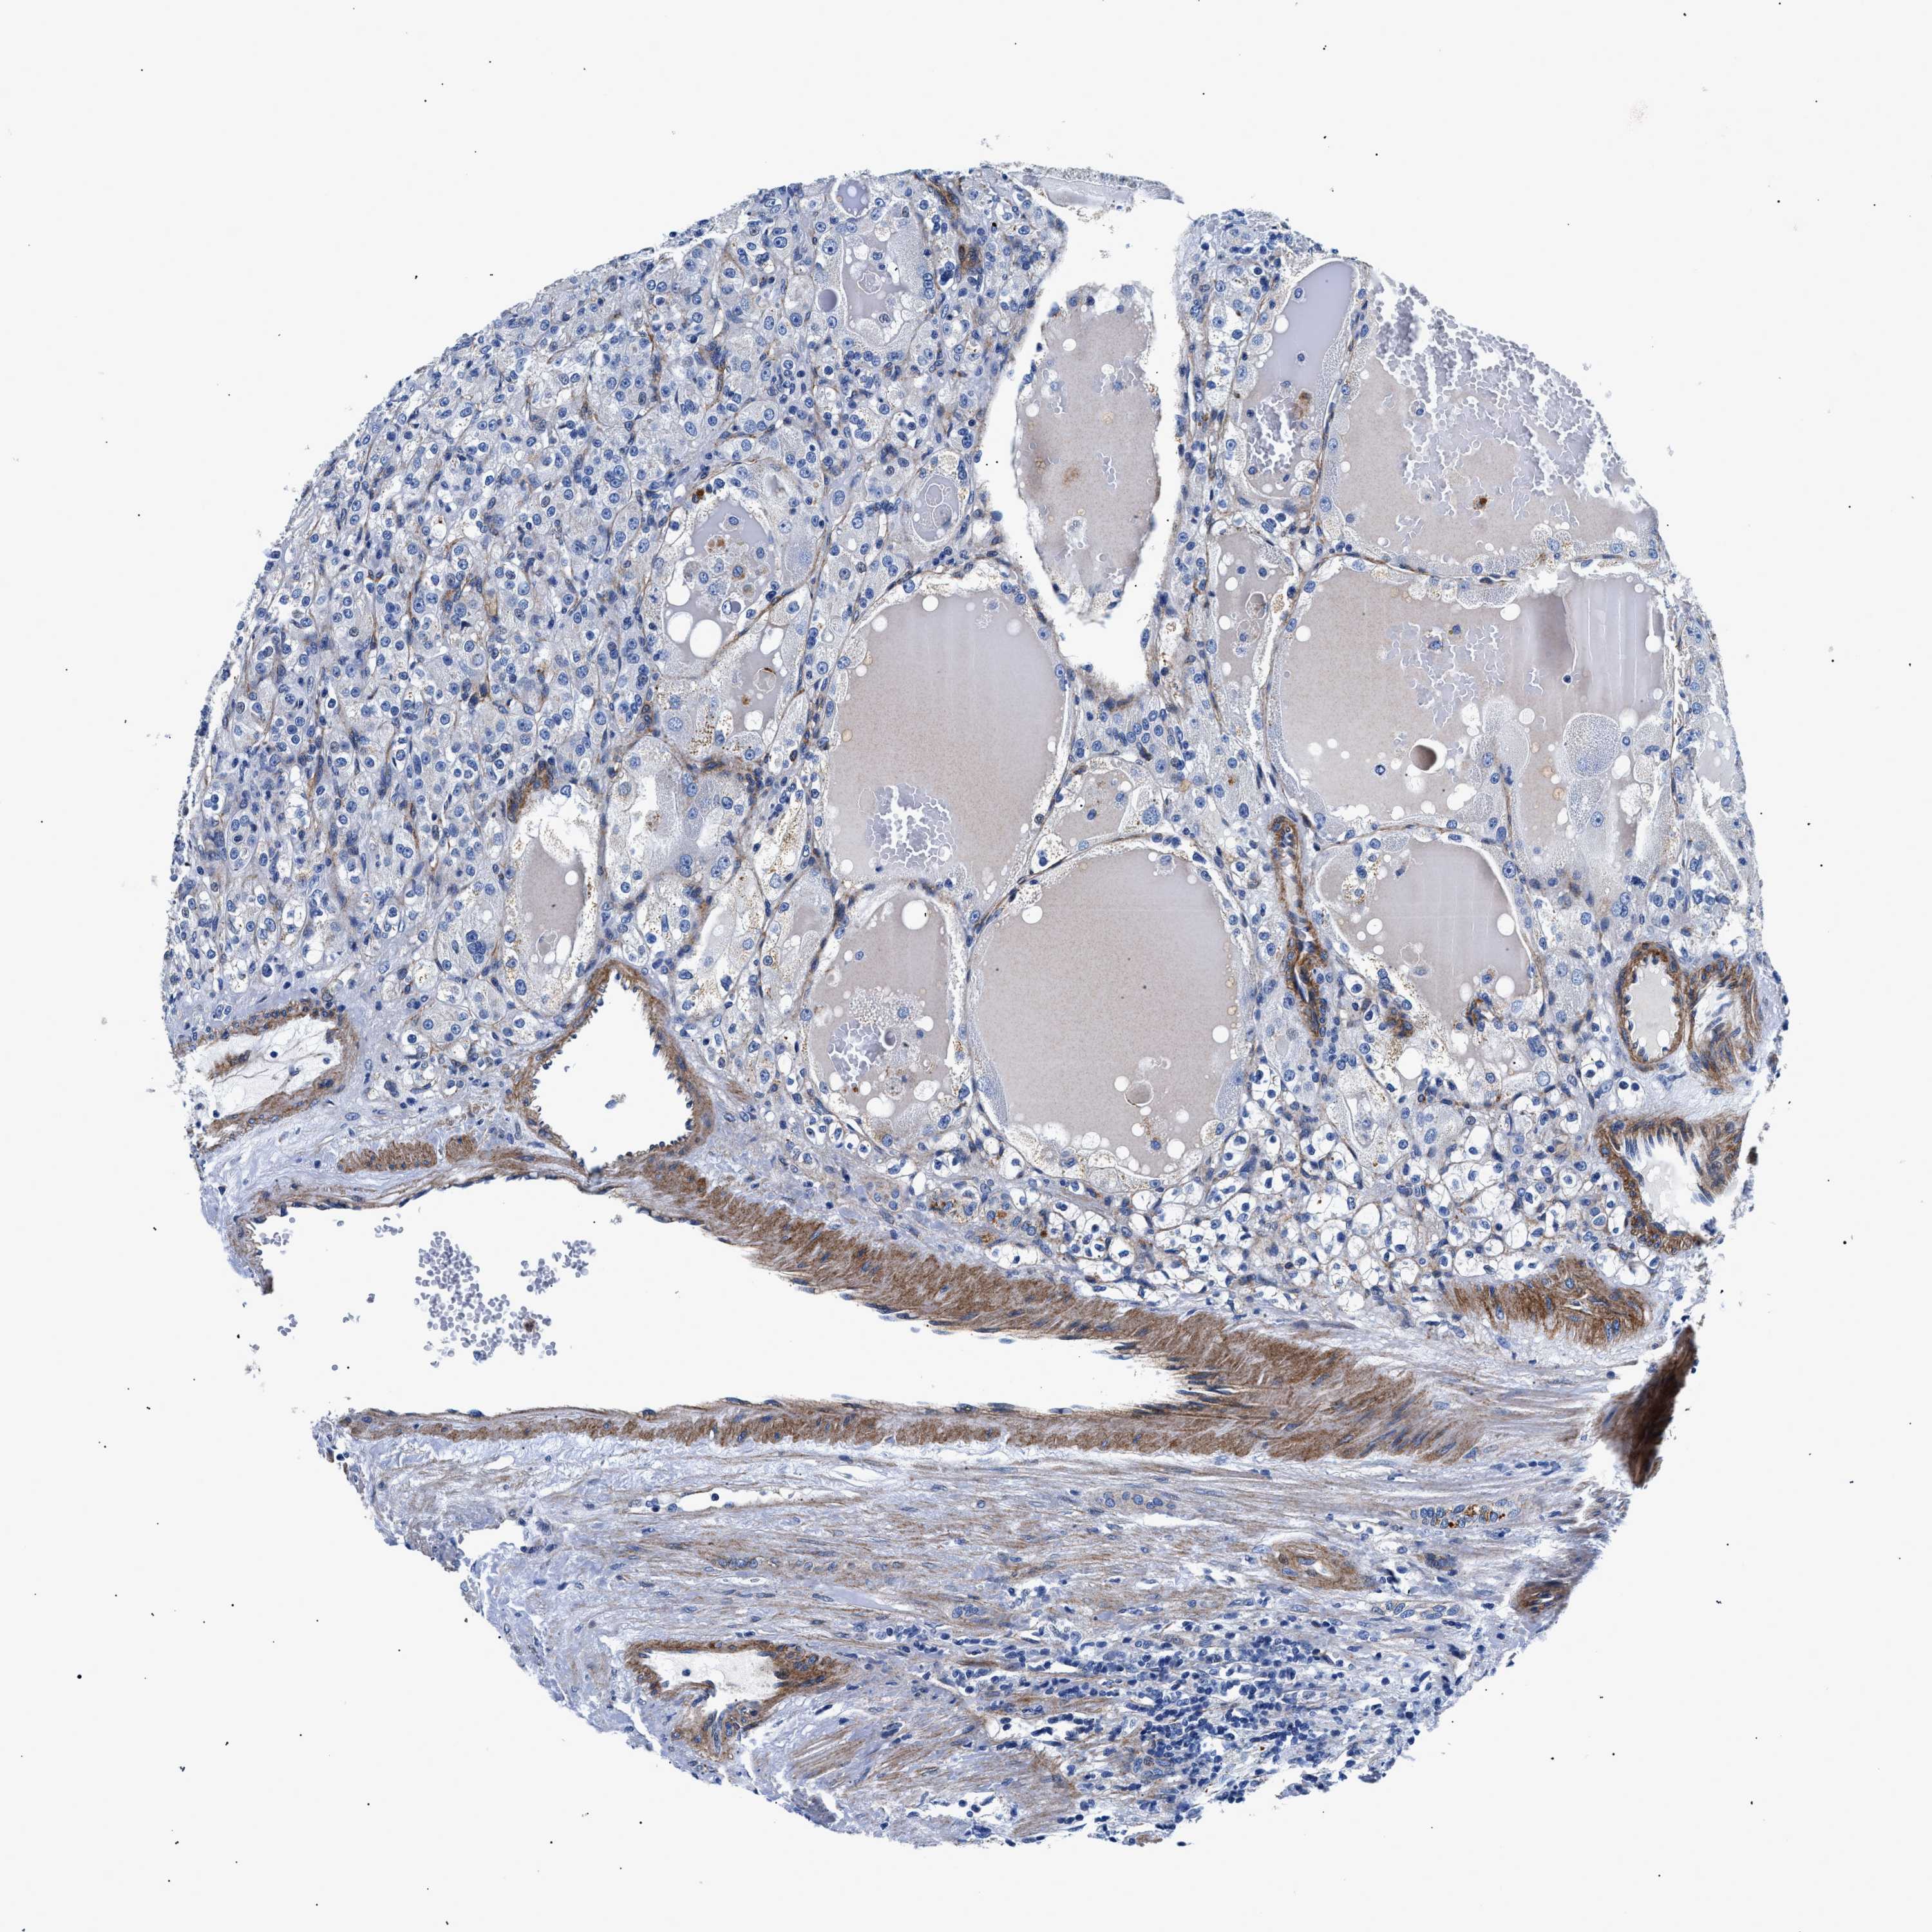

CANCER RENAL CANCER Show tissue menu

KICH TCGA KIRC TCGA KIRC VALIDATION KIRP TCGA PROTEIN RCC CPTAC PROTEIN EXPRESSION